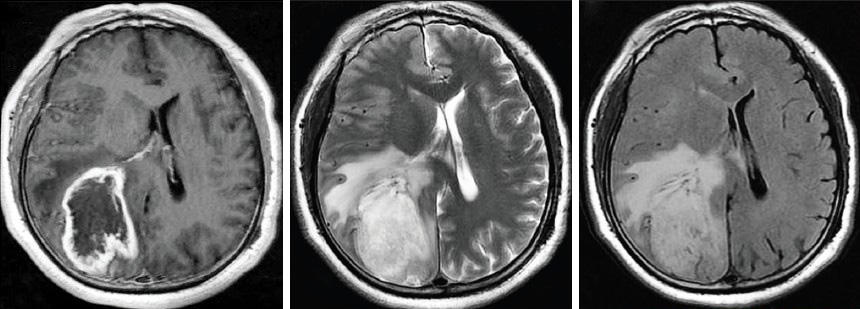

The image series above shows different MRI pictures of a patient diagnosed with an astrocytoma located in the left hemisphere. Astrocytomas, represent the most common type of primary brain tumours. They develop from star-shaped glial cells called astrocytes and can be classified into several sub-groups:

Low Grade diffuse astrocytoma

These tumours contain cells that grow slowly and may sometimes be completely removed through surgery. However, these tumours may be life threatening if they are inaccessible.

Anaplastic astrocytoma

These tumours grow more rapidly and contain cells with more malignant traits. Surgery followed by radiation, and sometimes chemotherapy, is used to treat anaplastic astrocytomas.

Glioblastoma multiforme (GBM)

As the name “multiforme” implies GBMs are known for their extensive cellular complexity. The tumours grow rapidly, invade nearby tissue and contain cells that are highly malignant. Doctors usually treat GBMs with surgery followed by radiation therapy and, chemotherapy. Glioblastomas multiforme are among the most common and devastating primary brain tumours that strike adults.